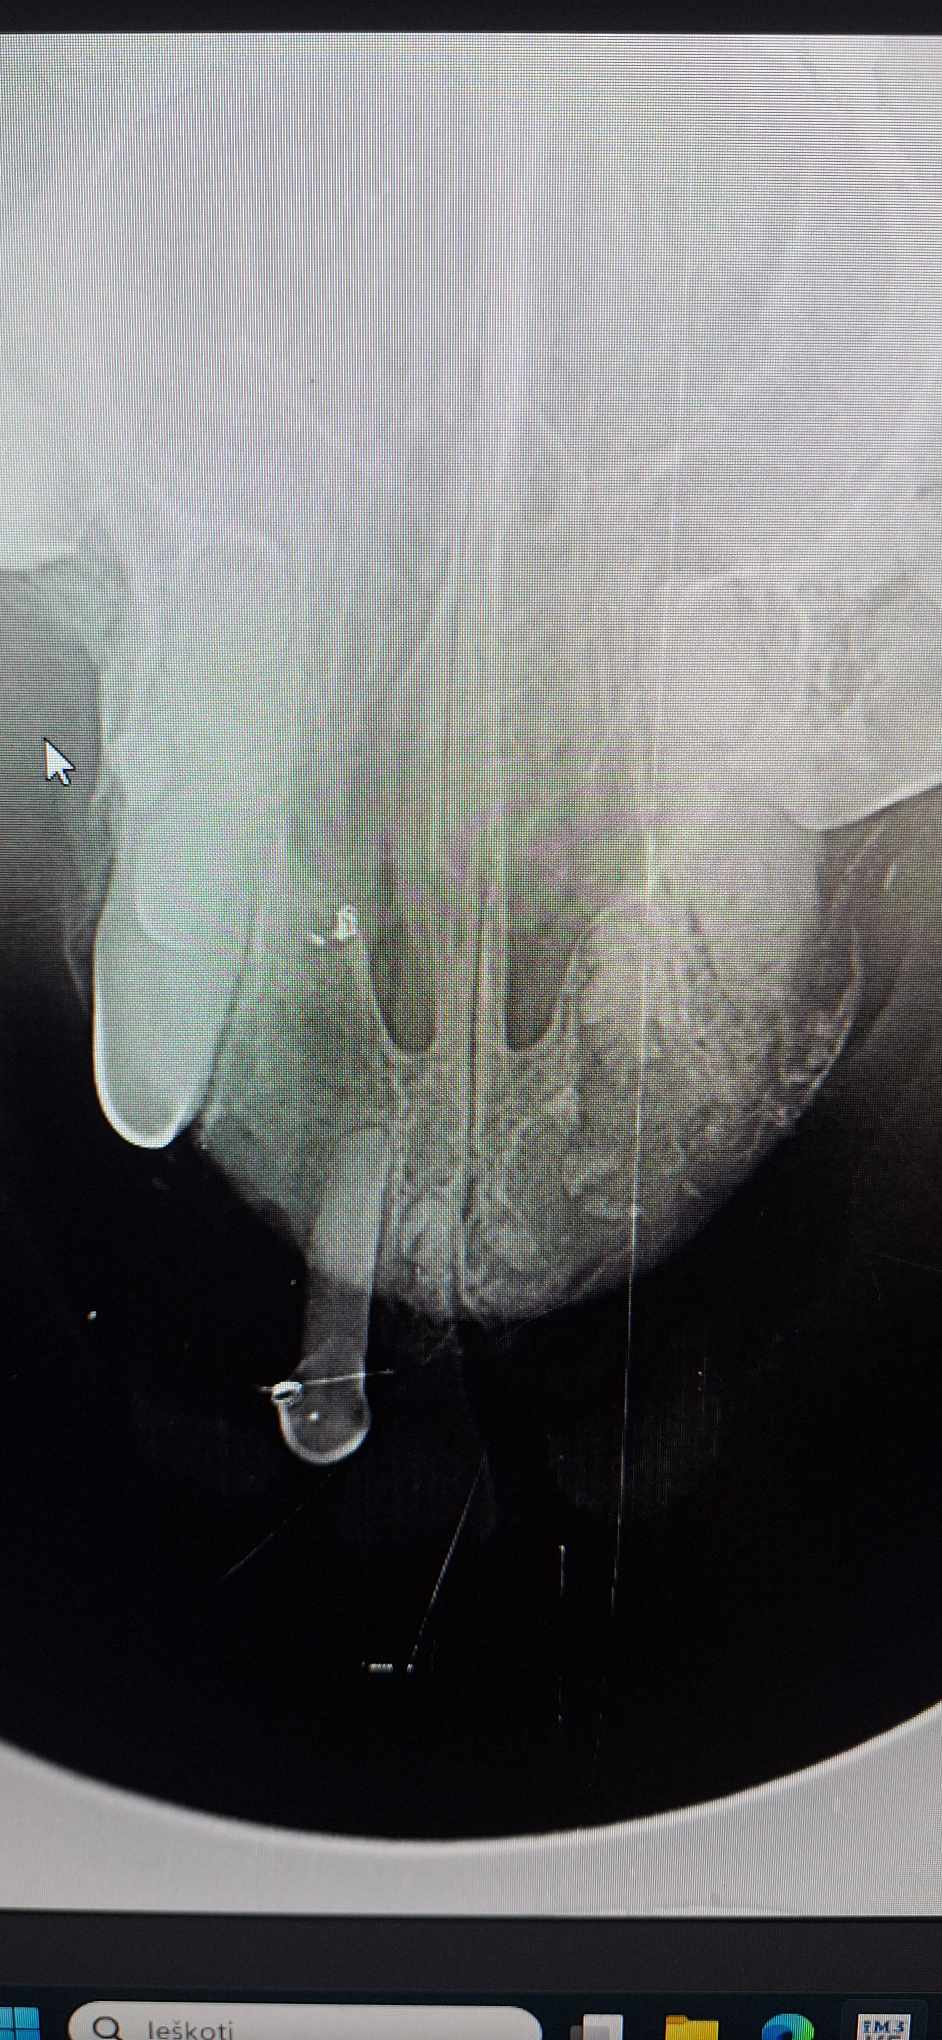

Rentgenas parodė ne tik perlūžusį bei sutrupintą žandikaulį, bet ir pakaušyje įstrigusį šratą, kurio įėjimo anga dar kraujavo… Kažkas šovė į seną mažą šuniuką, kas, galimai, turėjo įtakos įvykusiai nelaimei… Kam užkliuvo, kas toks beširdis?!

Sutvirtintas žandikaulis- ne paskutinė operacija. Dar, kai sugis, teks iš sutrupėjusios apatinio žandikaulio dalies ištraukti dantų šaknų nuolaužas.